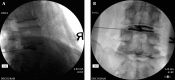

Figure 24.

Figure 24.. A, B, C and D: Spinal Cord stimulator Lead Placement for Low Back Pain as Well as Radicular Pain in a Post-Laminectomy Pain Patient Using a Dual Lead Configuration

The lesion is generated between the tips of the probes and provides a near complete coverage of the posterior annulus.